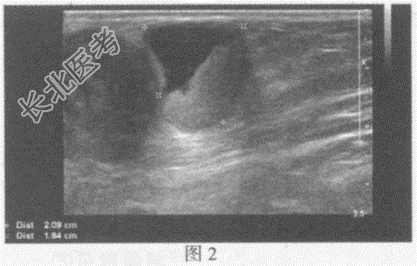

超声综合描述:左腹股沟区可见多个低回声(图1), 部分相互融合,最大3.5cm×2.1cm, 边界清晰,形态不规则, 内回声不均,CDFI: 内可见血流信号。左腹股沟区另可见多个不均质回声区(图2),最大2.1cm×1.8cm, 边界清晰,形态不规则, 内可见无回声区,CDFI: 不均质回声区内可见血流信号。